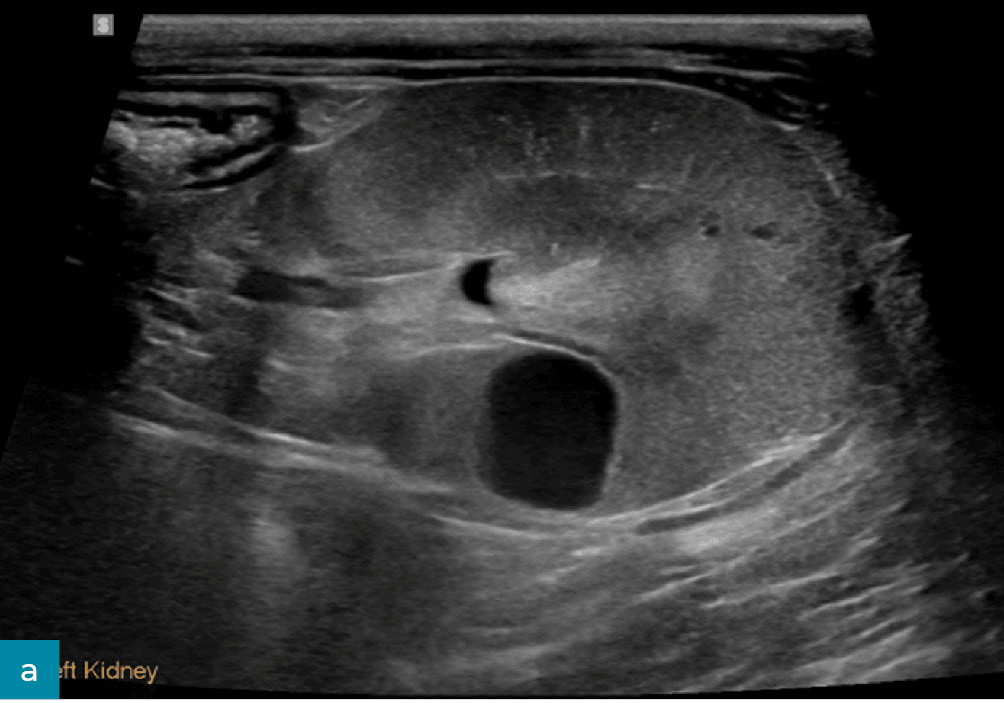

Poszerzenie miedniczki nerkowej (pielektazja)

Poza takimi czynnikami jak dożylna płynoterapia lub odmiedniczkowe zapalenie nerek zwiększone wydalanie moczu u pacjentów z przewlekłą chorobą nerek jest często związane z poszerzeniem miedniczki nerkowej.16 Pielektazja to nagromadzenie płynu i wtórne rozszerzenie miedniczki nerkowej wynikające z procesu niezwiązanego z niedrożnością (ryc. 8).8 Dla porównania wodonercze to rozszerzenie miedniczki nerkowej wtórne do niedrożności dróg moczowych. Pielektazja jest najczęściej symetryczna i obustronna, może jednak występować jednostronnie lub asymetrycznie w obu nerkach.3,16 U pacjentów z pielektazją i niewydolnością nerek wysokość miedniczki nerkowej zazwyczaj nie przekracza 3,4 mm u psów i 3 mm u kotów.16 Jeżeli poszerzenie miedniczki nerkowej jest większe, należy dokładnie ocenić drogi moczowe pod kątem nieprawidłowości, aby potwierdzić obecność innych procesów chorobowych, takich jak odmiedniczkowe zapalenie nerek lub wodonercze wtórne do niedrożności dróg moczowych.16

Ryc. 8. Obraz w projekcji poprzecznej prawej nerki psa, ukazujący łagodne poszerzenie miedniczki nerkowej (wysokość miedniczki nerkowej oznaczona wskaźnikami). Brak cech niedrożności.